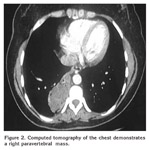

Multidetector CT was obtained after the administration of 2-4 mL/kg (maximum contrast doses 80 mL) non-ionic contrast agent with a concentration of 350/100 mg/dL (Iomeron 350, Bracco) via a subcutaneous antecubital vein at a rate of 3.5 mL/sec. Bolus tracking method was used. Acquisition was triggered automatically when the contrast reached the level of aorta. The images were sent to the workstation (Advantage Workstation, ADW 4.2, GE. Medical Systems). One of the patient?s multidetector CT angiography scan was? demonstrated Figure 1, 2.